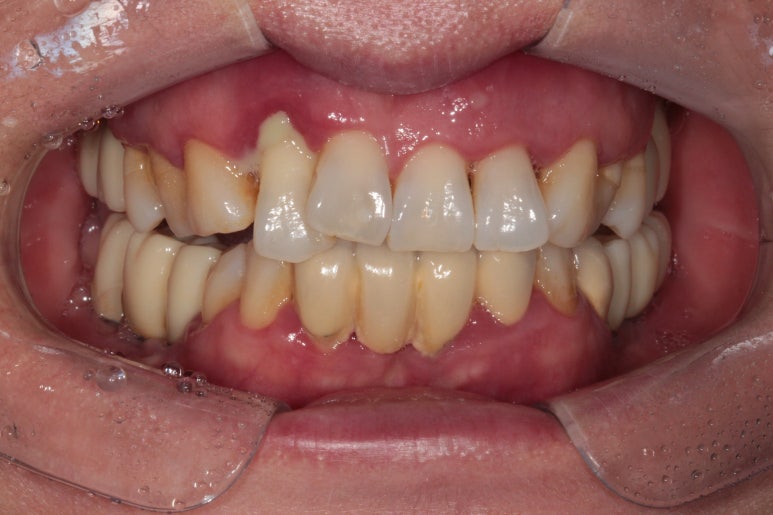

50대 여자 환자분입니다. 처음에 내원하셨을 때 정면 사진이에요.

딱 보아도 잇몸 상태가 참 좋지 않았습니다. ㅠㅠ 특히 위 앞니는 가만히 있어도 고름이 나오고 있는 상태지요..

만성치주염을 갖고 계신 환자분들은 이러한 상황을 조심하셔야 합니다.. 너무 방치되면 정말 임플란트를 심을 잇몸뼈가 하나도 남지 않을 수 있어요.... 그러다 진짜 틀니 하셔야 합니다!!...